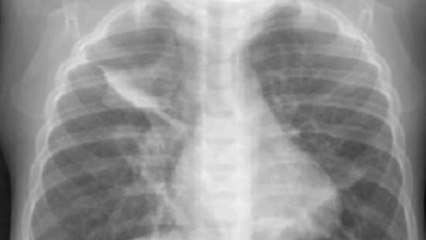

Dos mujeres trasplantadas comparten los pulmones de un mismo donante

Tras la operación Mercedes y Peregrina se consideran "hermanas de pulmón"